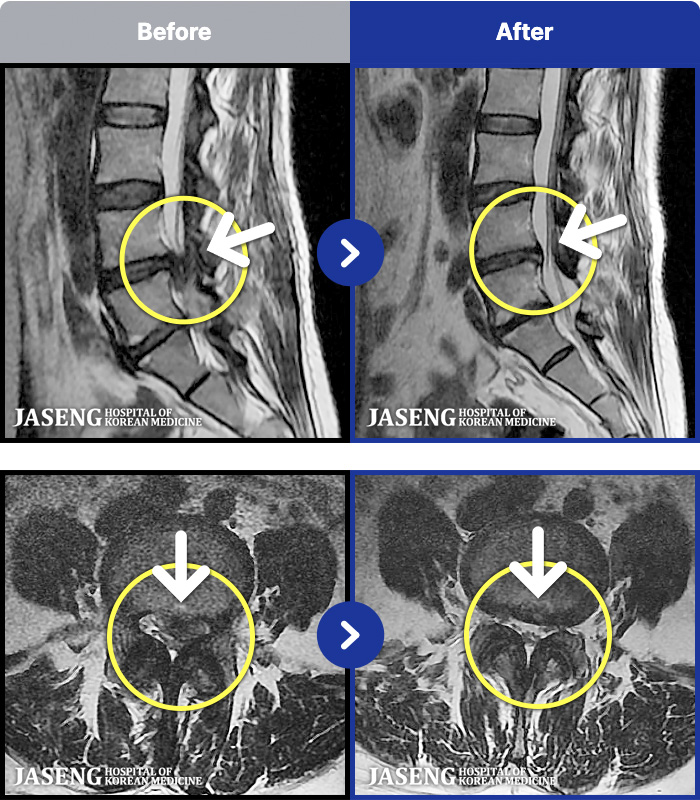

[] 23.11.11~25.06.04